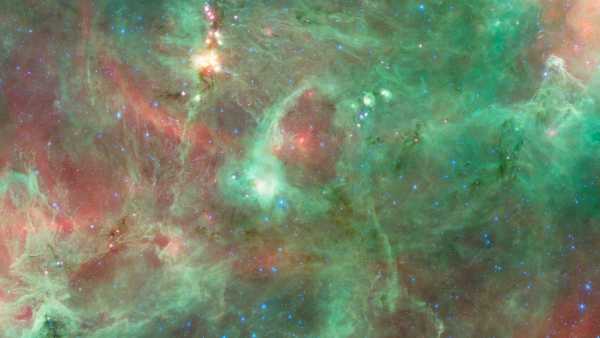

Комп'ютерна томографія грудної клітки чоловіка виявила кальцифіковані ділянки грудних м'язів, куди він раніше вводив олії для покращення м'язової маси. (Зображення надано: Markowska et al. BMC Nephrol 26, 476 (2025). (CC 4.0))

Чоловік загалом був стабільним, але медичний огляд показав помітні зміни в м’язах плеча та грудей, що відповідали порушенням, виявленим на сканах. Потім лікарі переглянули історію хвороби пацієнта, і він поділився важливою деталлю: приблизно 30 років тому він почав отримувати «невідомі внутрішньом’язові ін’єкції (ймовірно, що містять тестостерон)» у м’язи грудей та плечей для їх збільшення, згідно зі звітом про його випадок.

Аналізи крові показали, що рівень паратиреоїдного гормону, який контролює кальцій у чоловіка, був значно низьким, що виключає поширену гормональну причину високого рівня кальцію. У чоловіка також не було ознак прихованого раку в травному тракті, жодних відхилень при урологічному обстеженні та жодних ознак аутоімунного захворювання. Виключивши інші причини, медична бригада провела біопсію однієї з аномальних ділянок м'яза.

Діагноз: під мікроскопом м'яз був заповнений силіконополімерною речовиною на масляній основі та оточений щільними кальцієвими відкладеннями. Команда вчених дійшла висновку, що попередні ін'єкції чоловіка в м'язи, ймовірно, містили синтол, речовину, що складається переважно з олії, яка візуально «наповнює» м'язи, по суті, надуваючи їх, як водяні кульки.

У цьому випадку синтол викликав стійку реакцію на чужорідне тіло — організм, по суті, реагував на матеріал, який він не міг розщепити. З часом ця реакція призвела до рубцювання та кальцифікації, що призвело до накопичення великої кількості кальцію всередині м'яза. І зрештою цей кальцій потрапив у його кров.